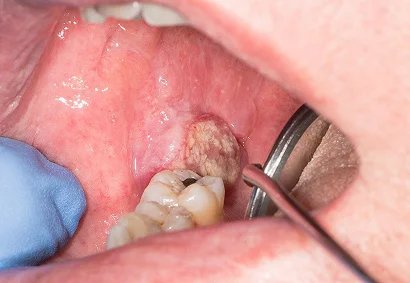

Management of very advanced oral cancer

Very advanced oral cancer often involves deep tissues of the mouth, jaw, or face, making treatment more complex. At this stage, patients may experience difficulty in eating, speaking, and even breathing. But with modern medical and surgical advancements, meaningful recovery is still possible. At Faith Hospital, treatment focuses on complete cancer control along with functional and aesthetic reconstruction. Each patient receives an individualized plan — combining advanced surgery, reconstruction, and rehabilitation — to help them return to normal life with dignity and confidence.